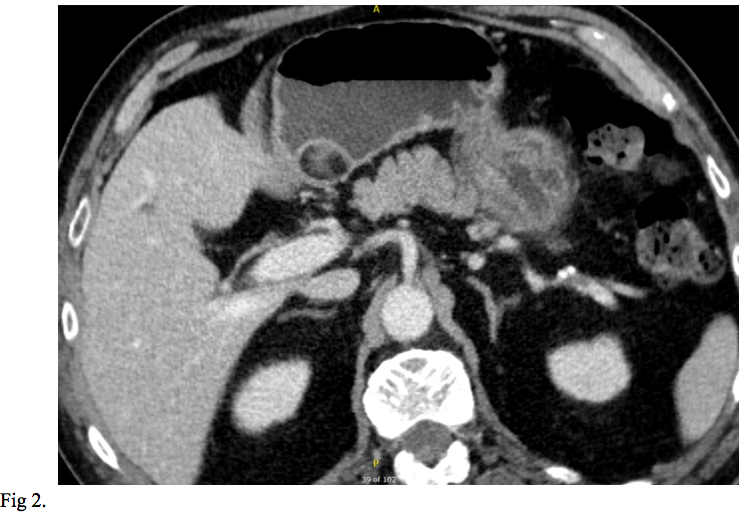

We report the case of a 66-year-old gentleman, known to suffer from high blood pressure, diabetes mellitus type 2, dyslipidemia, cervical and lumbar spondylosis, who presented to the emergency department with asthenia, pallor, melena. On physical examination, the patient was tachycardic with a heart rate of 120, and had a blood pressure of 100/60. He was pale but conscious and orientated. Cardiovascular and respiratory examinations were normal. His abdomen was soft, non-distended, bowel sounds were present and no palpable masses were felt. His laboratory investigations showed a mild normochromic, normocytic anaemia, low haematocrit, hyperglycemia, hypercholesterolemia. The patient was initially resuscitated and stabilized with intravenous fluids and proton pump inhibitors were initiated (iv 80 mg bolus and continuous infusion 8 mg/h). A naso-gastric tube was inserted which produced 300 ml of fresh blood. The patient underwent an urgent upper GI endoscopy which revealed an antral submucosal tumour with an ulcer over the mass. No active bleeding was seen during the procedure. A CT scan of the abdomen and pelvis highlighted a 30/20/18 mm oval shaped soft tissue lesion of fat density arising from the posterior wall of the stomach, with no associated lymphadenopathy. The liver, spleen, and pancreas all appeared normal (Fig 1,2). EUS has been performed and revealed a 30/18 mm intensely hyperechoic lesion continuous with the submucosal layer of the GI tract wall. The lesion was also soft on elastography, and as all the features were suggestive of a benign lesion, tissue sampling was not performed at that stage (Fig 3,4). The patient’s case was discussed at the Tumor Board meeting. The joint decision was to proceed with an exploratory laparoscopy and resect the benign mass. Histopathological examination confirmed the diagnosis of lipoma (Fig 5,6).

Regarding our case, based on the endoscopic appearance and location of the SELs, gastrointestinal stromal tumor (GIST), a neoplastic lesion with malignant potential was the most likely diagnosis. Differential diagnosis included surely benign lesions such as a lipoma, leiomyoma or schwannoma. The diagnosis of lipoma was suspected on abdominal CT scan and was confirmed by EUS. The joint decision to proceed with an exploratory laparoscopy and resect the benign mass was made based on the latest recommendation of the American Society for Gastrointestinal Endoscopy (ASGE). The suggestion of ASGE was that symptomatic GI lipoma should be resected or followed up.